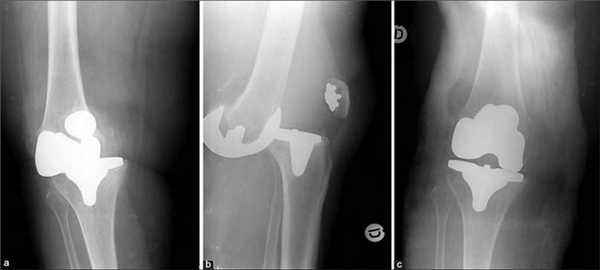

Сравнение двух типов операций.

Отличия от тотального эндопротезирования

Длительное время ТЭКС (тотальное протезирование коленного сустава) признавался ведущим методом при лечении остеоартроза. Какие же преимущества имеет одномыщелковое эндопротезирование:

- Гораздо меньший объем хирургического вмешательства;

- Быстрый восстановительный период (уже через несколько месяцев пациент может возвращаться к своим повседневным физическим нагрузкам);

- Менее выражен болевой синдром (как в покое, так и при интенсивной физической нагрузке);

- После частичного эндопротезирования люди вдвое реже жалуются на трудности при использовании автомобиля, чем после тотального;

- Вдвое меньше случаев ограничения сгибания в коленном суставе и контрактур;

- Гораздо чаще людям с частичным эндопротезом доступно положение сидя на корточках, посадка и выход из автотранспорта, наклон и подъем предметов с пола, бег.